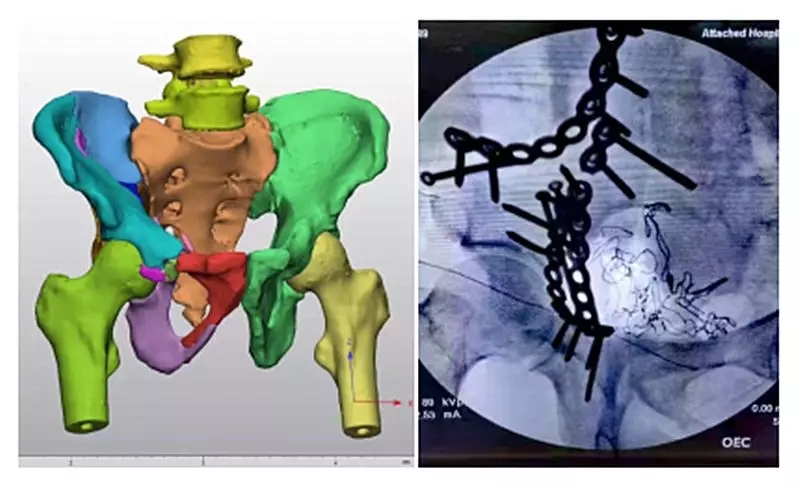

近日,我院骨外科收治一名复发骨盆骨折患者,男性,47岁,主因摔伤3小时右髋部疼痛、肿胀伴活动障碍入院。诊断为:右侧髂骨骨折、右侧髋臼粉碎性骨折、右侧耻骨骨折。经过仔细阅片后,骨外科主任焦建宝、副主任医师薛金伟认为该患者右侧骨盆存在多处骨折,且骨折断裂、移位严重。有必要应用三维可视化辅助进行术前规划及术中指导。我院医学3D影像打印中心副主任张珂经重建后发现本例患者右侧髂骨、髋臼、耻骨碎成13处之多,且多处碎骨存在移位,移位角度偏大。三维重建及手术过程都极为复杂。张珂针对该例患者连夜进行科研攻关,在最短时间重建出准确的骨盆可视化模型,并上传至三维数字云平台方便手术医生随时查看。经过精心术前规划与演练,薛金伟为患者行右侧髂骨、髋臼、耻骨骨折切开复位内固定术。患者手术顺利,手术时间较传统阅片定位后再手术的方法大大缩短,术中C型臂透视可见骨折对位、对线良好,内固定位置良好、稳定。手术结果符合术前三维重建规划预期。目前患者骨折复位质量及骨盆功能均得到良好恢复。

医学3D影像打印中心成立两年多以来,与骨外科专业多次合作,病理骨分割相对传统方法效率已有了极大的提高。三维可视模型辅助手术有如下优势:立体三维模型能够弥补平面影像所造成的图像缺失,使医生从视觉、触觉角度深入细致观察骨折线位置、走向、移位方向并可进行长度、角度、体积等参数精准测量,在此基础上制定的手术方案更加精准、详实;术者能从多角度细致观察骨折模型,设计出最适合患者的手术入路,有助于缩短手术切口长度,实现有限显露精准治疗;能根据体外模拟技术进行钢板预弯,最大程度促使其与骨折面贴合,从而缩短手术时间、减少术中出血量,改善骨折复位效果,显著降低手术并发症发生。